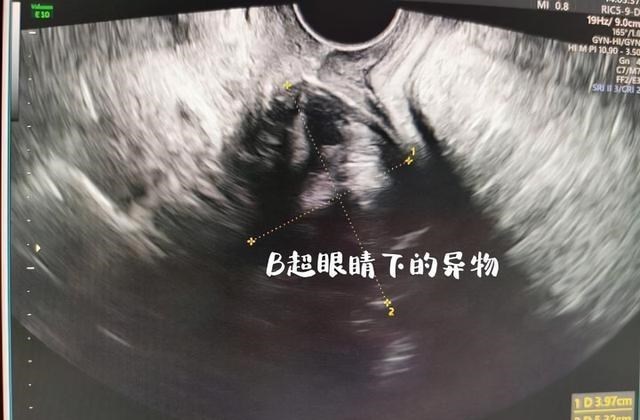

为了确定小杨的病情 , 医生首先为小杨做了B超检查 , 发现体内确实存在异物 。

但难题也随之而来 , 由于这个瓶盖表面太光滑 , 不好找着力点 , 用普通工具 , 很难取出 。

加上一个月时间的停留 , 瓶盖已经和身体发生了一些反应 , 下体明显发炎 , 都出现了一些异味 , 只能采取其他办法 。

然后 , 谨慎的医生又为小杨做了超声检查 , 确定了异物的具体位置 , 幸运的是 , 虽然异物停留时间较长 , 但位置并不深 。

医生和小杨商量 , 可以借助B超 , 慢慢将异物取出 。